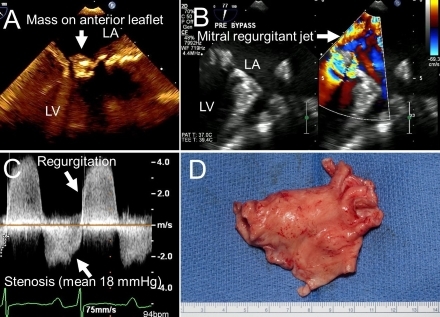

A 40-year-old woman presented with a 3-month history of dyspnea. A murmur was found on examination. Echocardiography reported moderate mitral stenosis and regurgitation with diffuse thickening and calcification of the anterior mitral leaflet (Fig1.A), thought to be due to rheumatic disease. She had runs of supraventricular tachycardias not controlled with diltiazem. Her dyspnea progressively worsened; transesophageal echocardiography(TEE) showed severe mitral stenosis and mitral regurgitation (mean gradient 18 mmHg; Fig1.B) with a dense CW Doppler (Fig 1.C) and a mass on left atrial free wall. Cardiac MRI revealed diffuse left atrial thickening with delayed enhancement of the left atrium, left atrial appendage, and extending into the right upper and left inferior pulmonary veins. The mass was initially suspected to be a thrombus. She was placed on rivaroxaban and scheduled to undergo mitral valve replacement.

When she presented to our emergency department with dizziness she was found to have paroxysmal atrial fibrillation and pulmonary embolism. On admission she had an intermittent opening snap and a 1/6 mid-diastolic rumble with a 2/6 holosystolic murmur at the apex. Work-up for infectious disease and antiphospholipid syndrome was negative. NT-proBNP was mildly elevated. At surgery the mass invaded the mitral valve and the anterior, septal, and superior part of the left atrial lateral wall and could only be partially excised (Fig1.D). Pathology showed high-grade undifferentiated pleomorphic cardiac sarcoma .